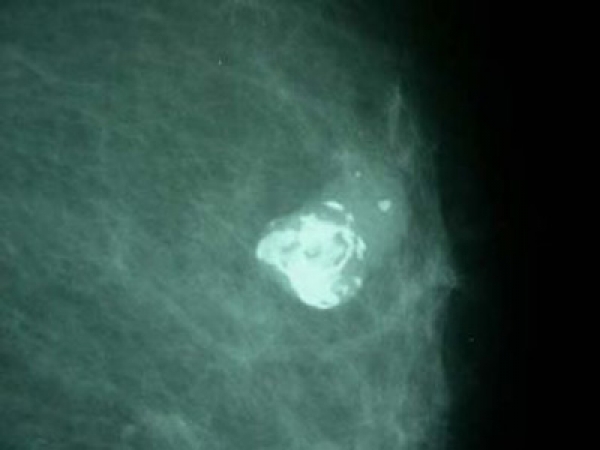

Galéria k článku Kedy je čas na mamografiu?